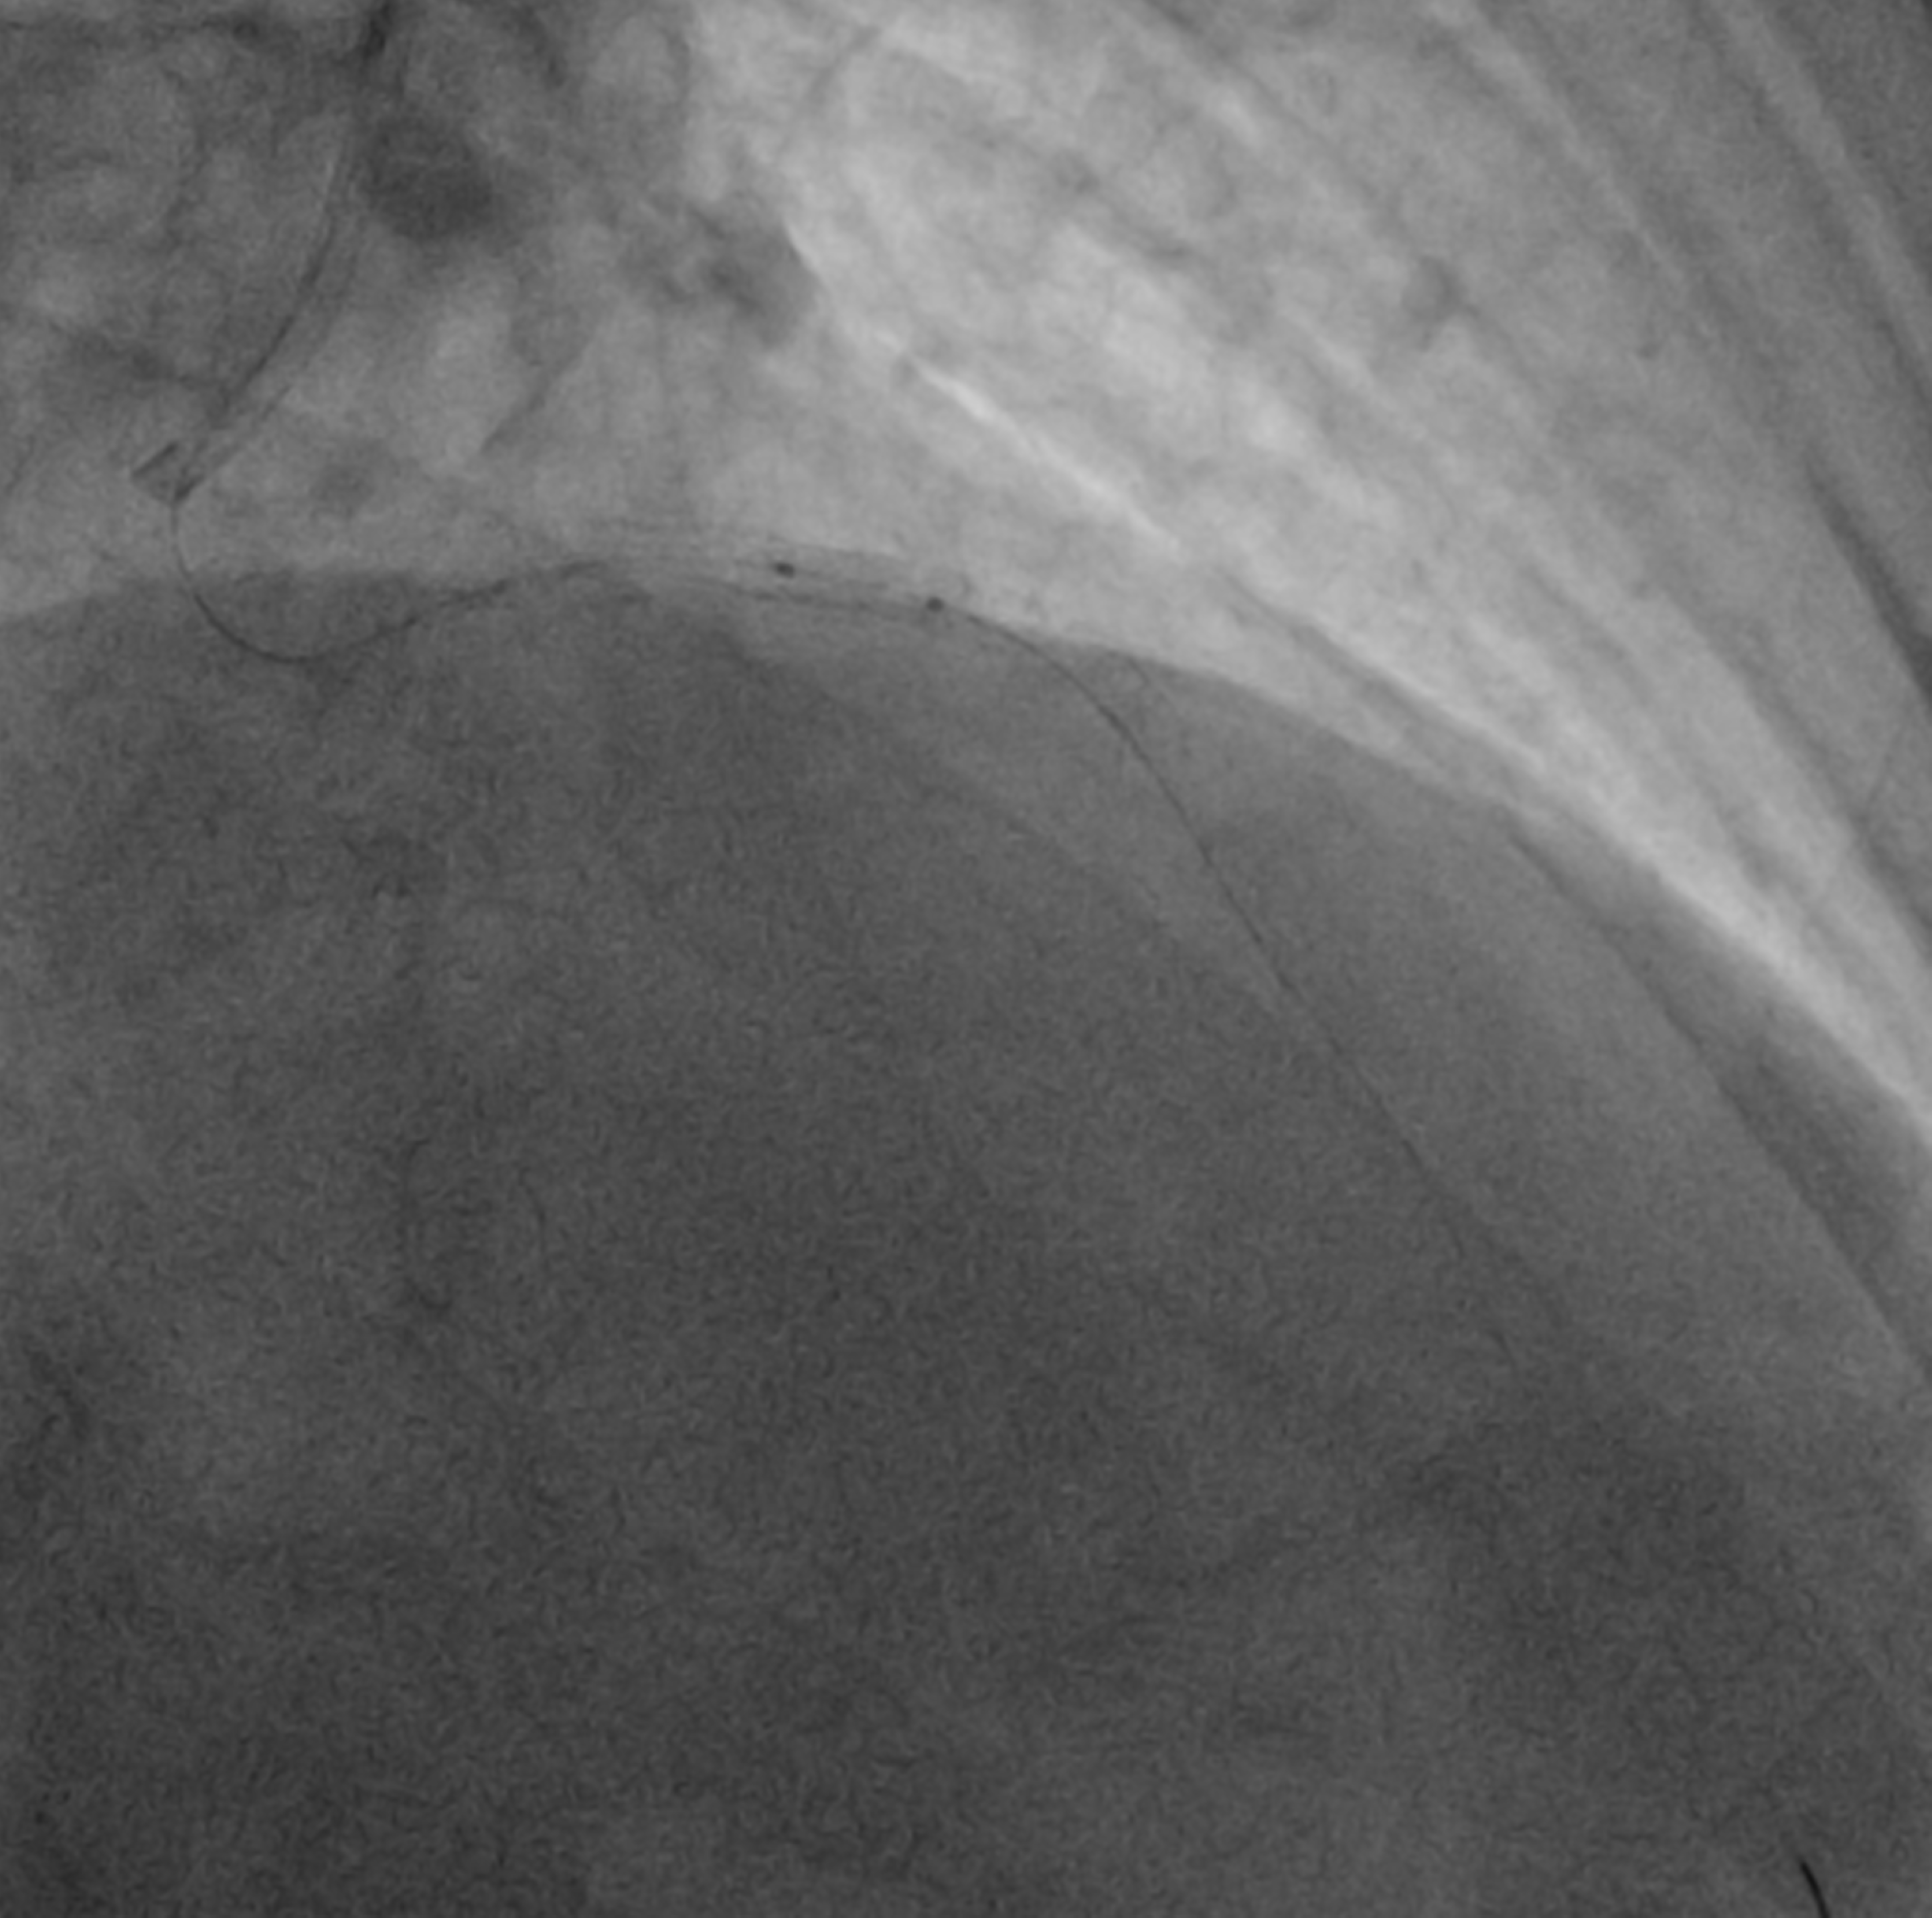

The LMCA was engaged with 7F JL 3.5 guiding catheter through right radial artery approach. The LAD lesion was crossed with one 0.014 wire and another 0.014 wire was placed in LCX. Than ostial to mid LAD lesion was sequentially predilated with 2.5x15 mm balloon, 3.0x10 mm Wolverine cutting balloon and 3.0x20 mm balloon after IVUS evaluation. After checking a 3.5x40 mm DES was positioned from LMCA to LAD. While positioning the stent patient developed VT, so immediately DC-cardioversion and chest compression was given. During this guide catheter was automatically disengaged and everything came out of coronaries. Again after careful guide catheter engagement the DES of 3.5x38 mm Ultimaster nagomi was deployed from LMCA to LAD. Than POT was done to LMCA stent with 5.0x8 mm NC balloon and LAD with 3.5x20 mm NC balloon. As LCX was dominant vessel, so kissing was done to distal LMCA with 3.5x20 mm NC balloon in LAD and 2.5x12 mm balloon in LCX.As IVUS revealed under expanded LAD stent so post dilatation done with 3.5x8 mm NC balloon at 16 atm pressure, than balloon failed to deflate. Gentle traction was applied to inflated balloon keeping negative suction ,but failed. Patient again developed VT, so DC-cardioversion was given. Trying to rupture the balloon with reverse end of BMW wire through OTW balloon, not worked. Than we used saline instead of dye with two indefaltors in three ways and negative pressure was given and that worked. Than procedure was completed with another balloon.